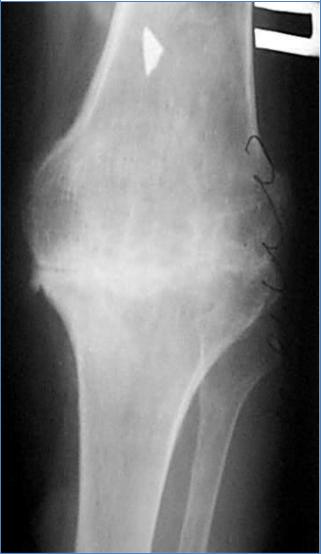

Анкилоз

Анкилоз - “зарастание” сустава, закрытие суставной щели.

Вначале развивается фиброзный анкилоз, который затем преходит в костный.

Пример – анкилоз коленного сустава, фиброзный, начальная фаза костного анкилоза.